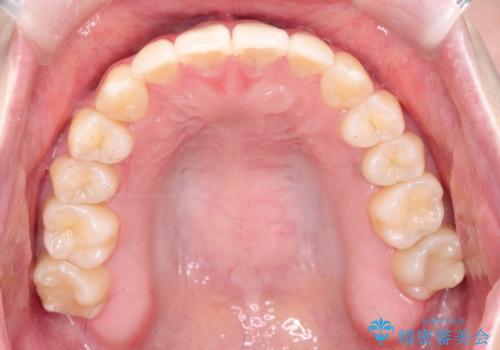

【インビザライン】歯を抜かずにできるだけ前歯を下げたい

- 前歯の前突を主訴に来院されました。

インビザライン を用いて、歯並びの改善を行うことができました。